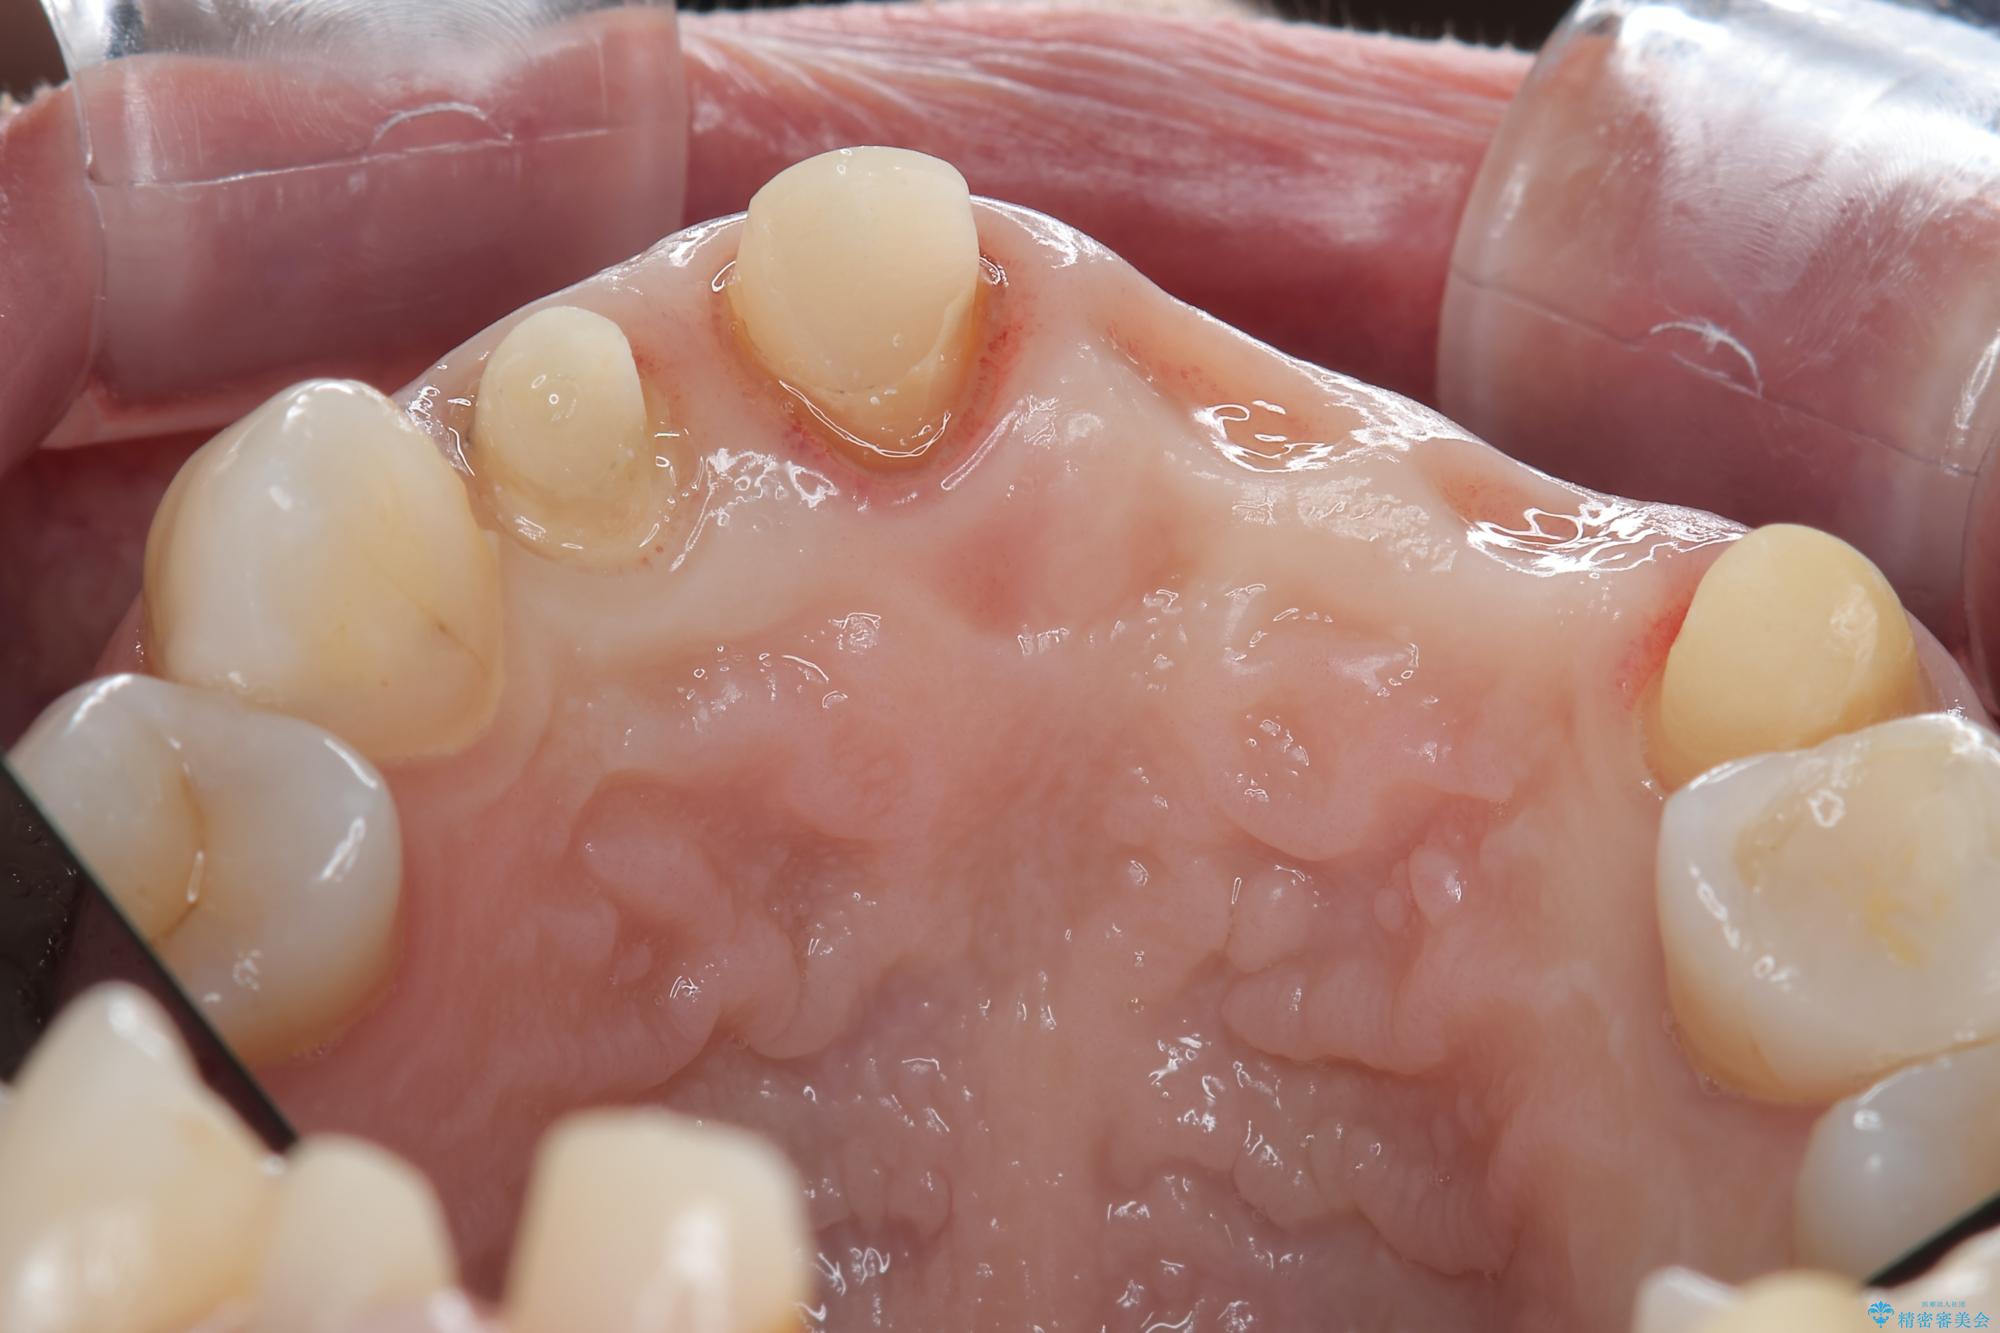

一見して問題ないように見える左側の2前歯は、セラミックを除去してみると亀裂や虫歯の再発が見られました。

治療前

歯槽堤保存術を併用したブリッジ治療 治療前画像 歯槽堤保存術を併用したブリッジ治療 治療前画像 歯槽堤保存術を併用したブリッジ治療 治療前画像 歯槽堤保存術を併用したブリッジ治療 治療前画像 歯槽堤保存術を併用したブリッジ治療 治療前画像 歯槽堤保存術を併用したブリッジ治療 治療前画像 歯槽堤保存術を併用したブリッジ治療 治療前画像 歯槽堤保存術を併用したブリッジ治療 治療前画像 歯槽堤保存術を併用したブリッジ治療 治療前画像 歯槽堤保存術を併用したブリッジ治療 治療前画像